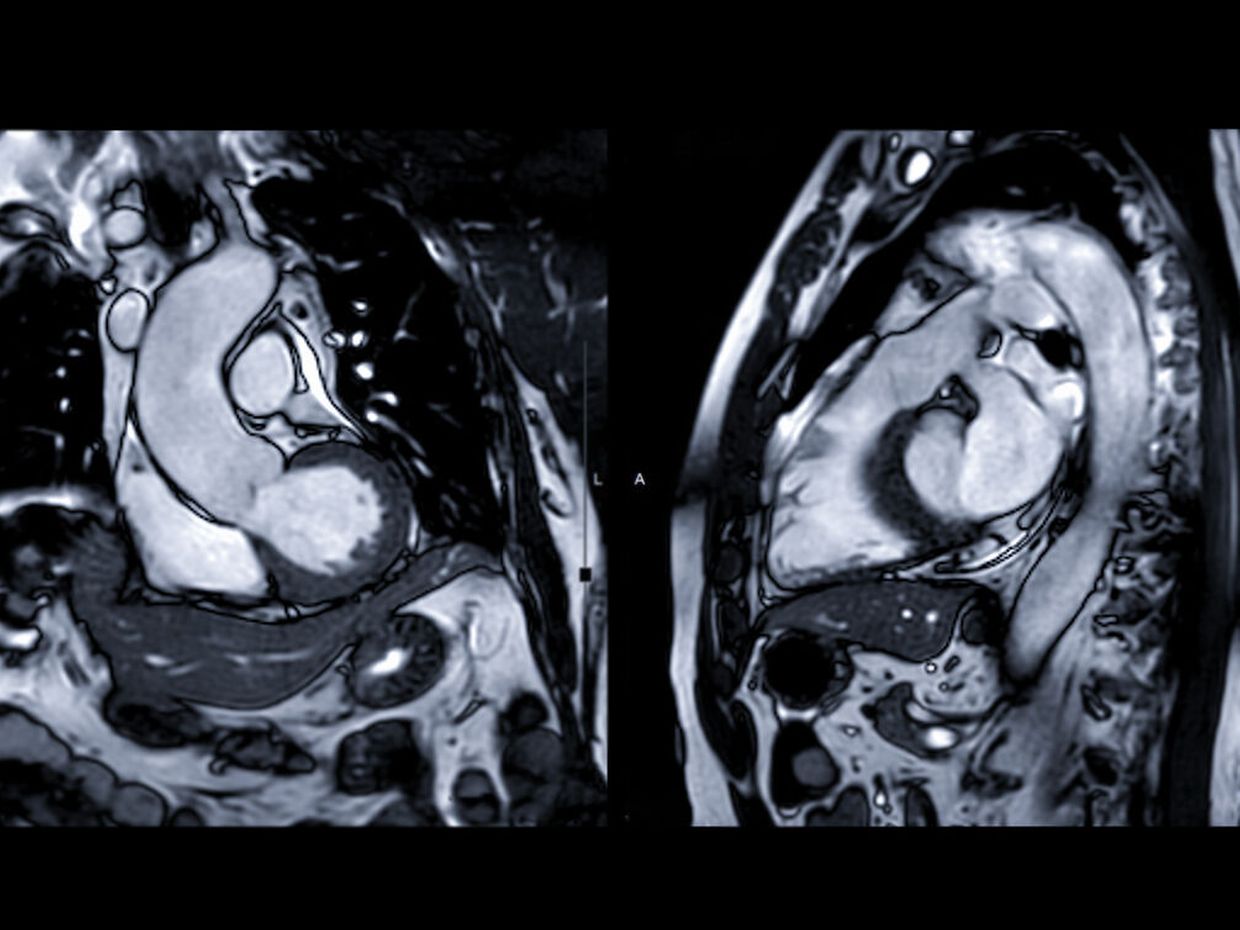

Sie kennen die Stärken und Schwächen der kardialen Magnetresonanztomografie (MRT) in der Diagnostik seltener hypertropher Kardiomyopathien, sowie deren Möglichkeiten in der Gewebecharakterisierung und zur Verlaufskontrolle.